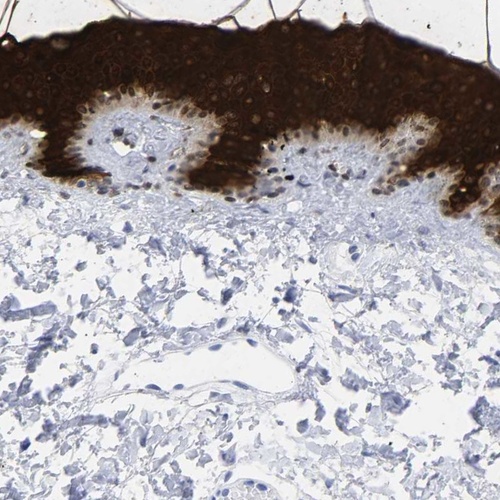

Immunohistochemistry analysis in human skin and kidney tissues using Anti-KRT1 antibody. Corresponding KRT1 RNA-seq data are presented for the same tissues.